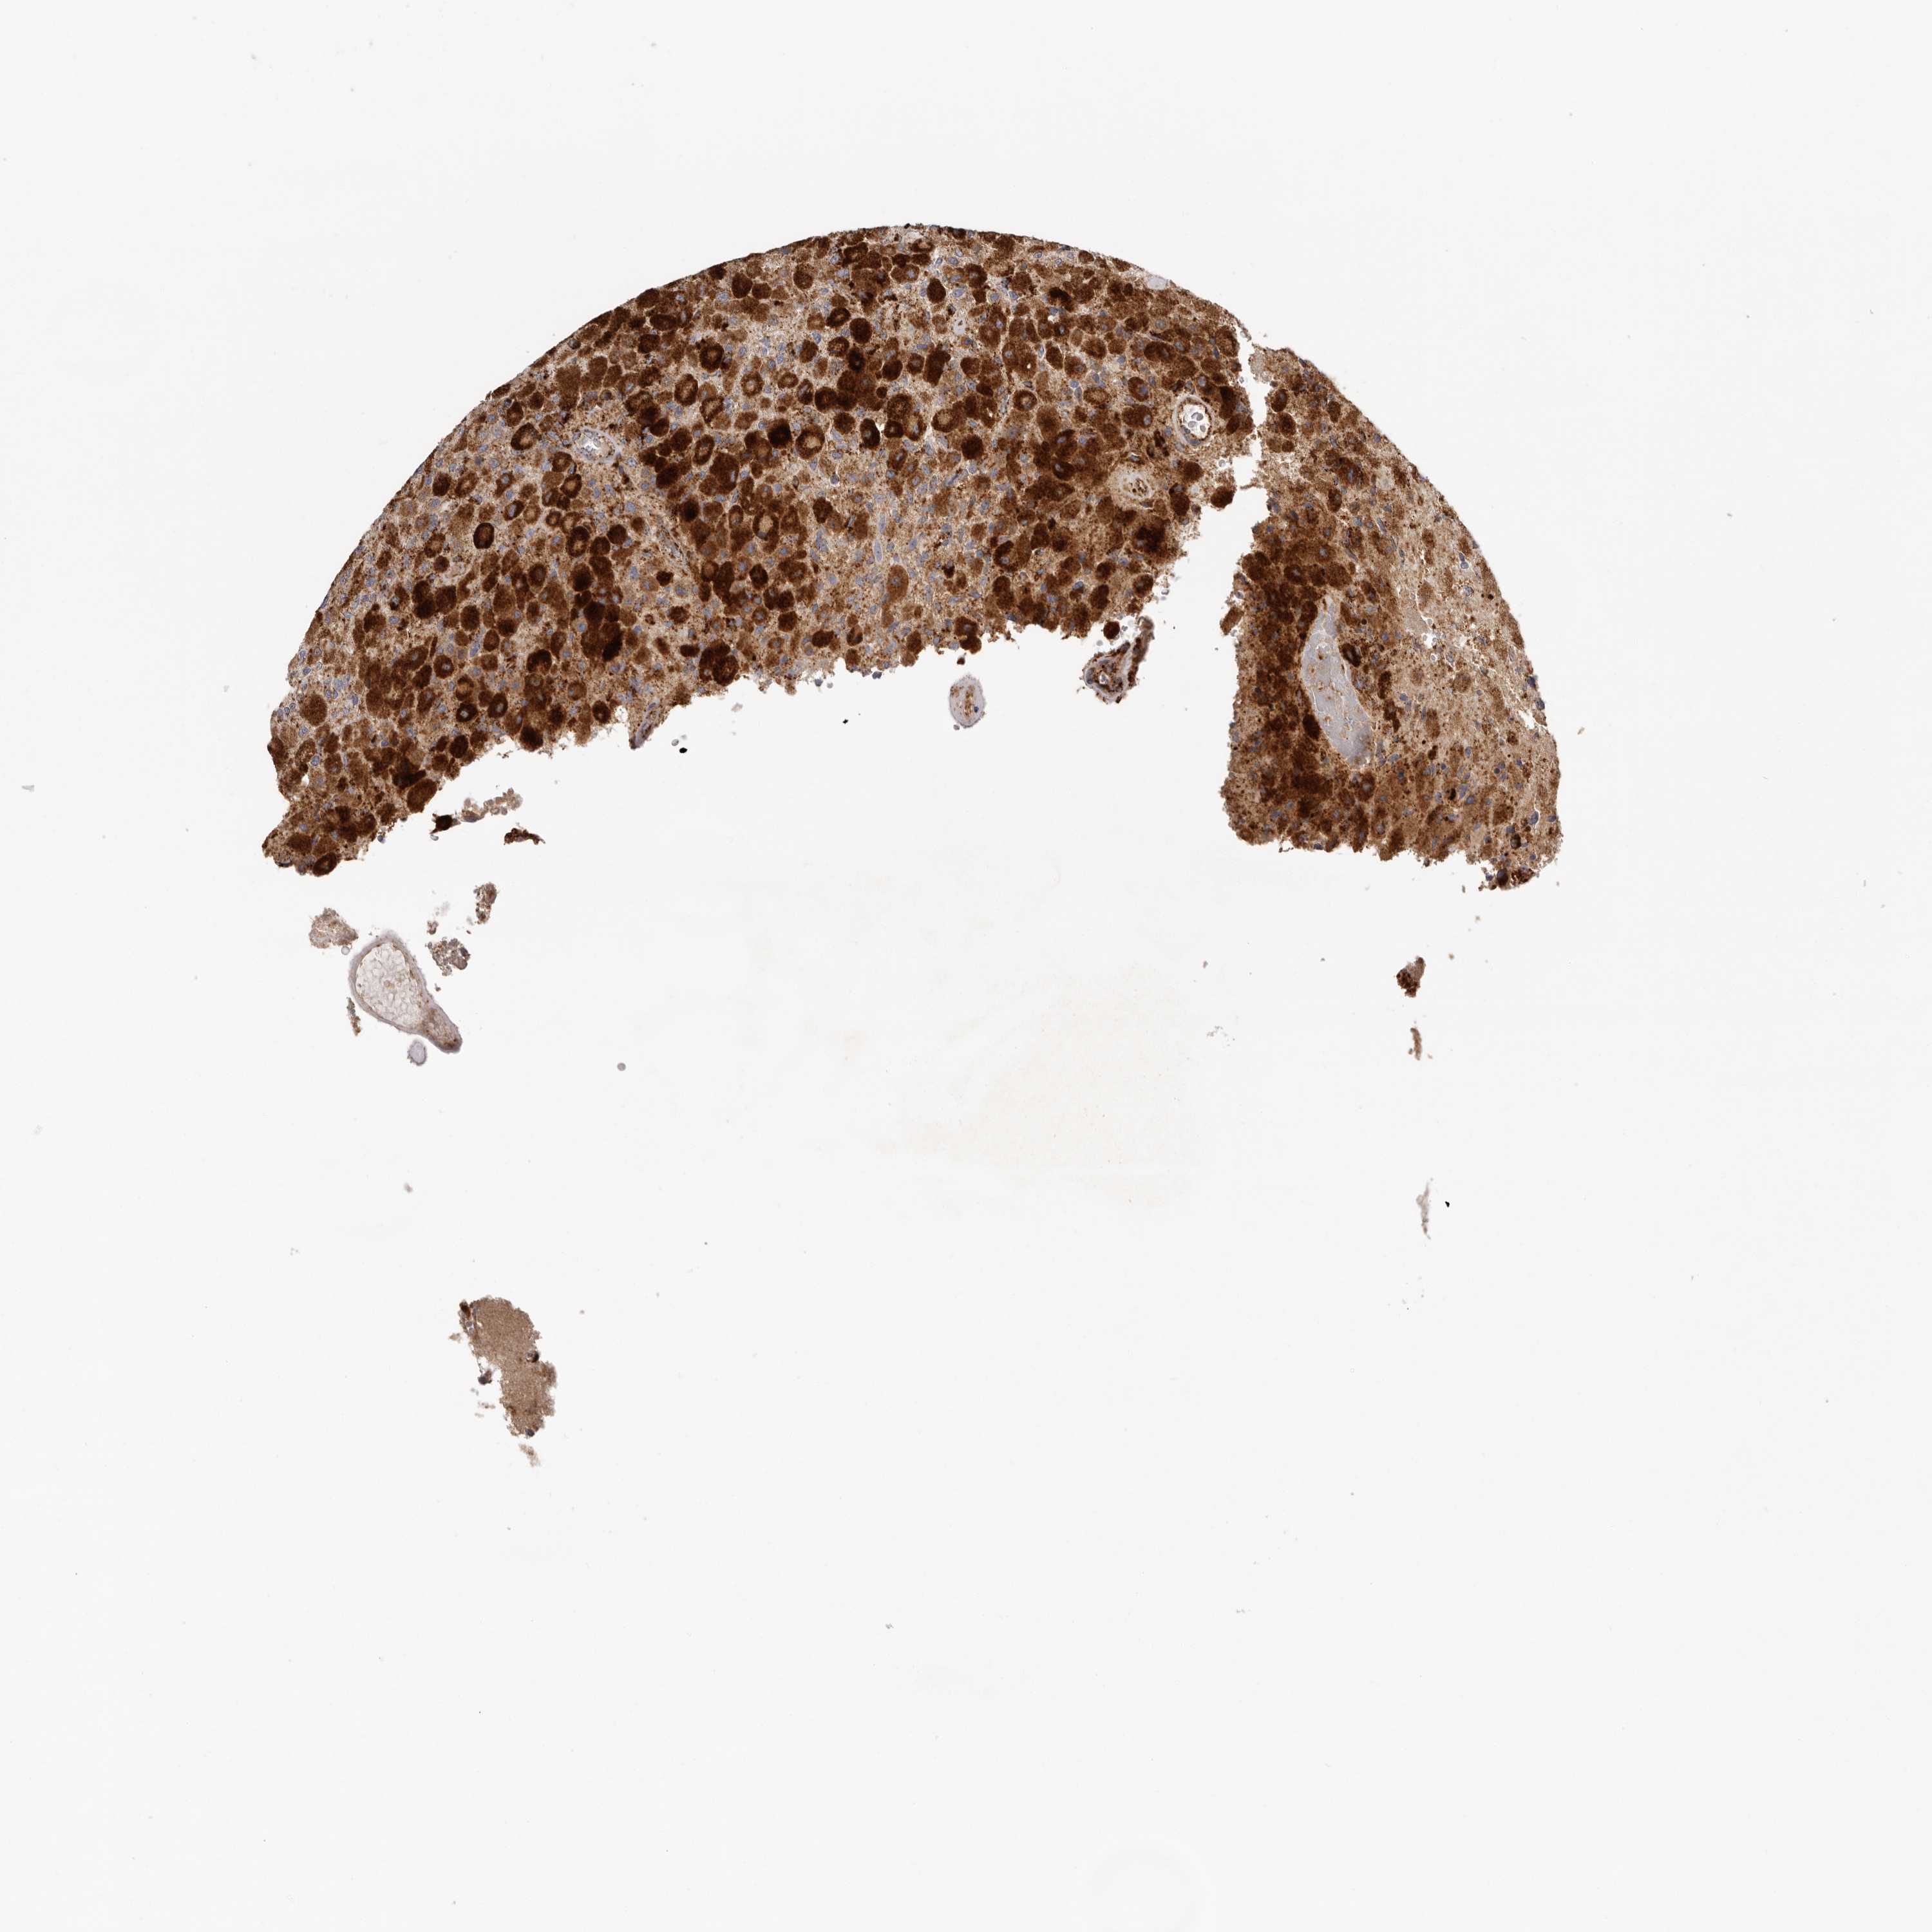

GLIOMA - Protein expressioni

A mouse-over function shows sample information and annotation data. Click on an image to view it in a full screen mode. Samples can be filtered based on level of antibody staining by selecting one or several of the following categories: high, medium, low and not detected. The assay and annotation is described here.

Note that samples used for immunohistochemistry by the Human Protein Atlas do not correspond to samples in the TCGA dataset.

Antibody stainingi

Antibody staining in the annotated cell types in the current human tissue is reported as not detected, low, medium, or high, based on conventional immunohistochemistry profiling in selected tissues. This score is based on the combination of the staining intensity and fraction of stained cells.

Each image is clickable and will lead to virtual microscopy that enables deeper exploration of all samples and also displays staining intensity scores, fraction scores and subcellular localization as well as patient and tissue information for each sample.

Antibody HPA008763

Antibody HPA028747

Antibody CAB019394

Staining

High

Medium

Low

Not detected

Intensity

Strong

Moderate

Weak

Negative

Quantity

>75%

75%-25%

<25%

None

Location

Nuclear

Cytoplasmic/membranous

Cytoplasmic/membranous,nuclear

Glioma, malignant, High grade

Glioma, malignant, Low grade